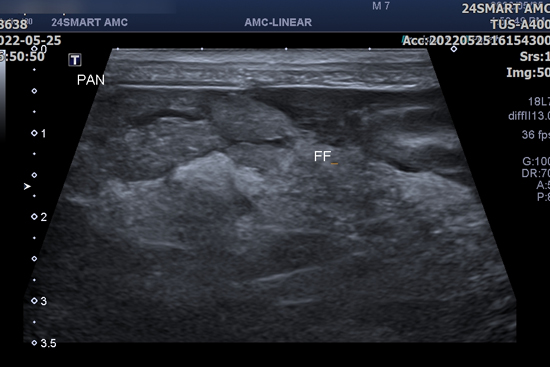

단백 소실성 장병증 (PLE, Protein losing enteropathy)

비정상적으로 장에서 단백질이 소실되는 질환을 의미합니다. 다량의 단백질이 장을 통해 소실되기 때문에 저단백혈증이 발생하게 되고 이러한 저단백혈증이 심하게 진행되는 경우에는 저알부민혈증에 의해 혈관 내 삼투압이 감소하여 흉수와 복수 등 체강 내로의 액체 저류가 발생하게 됩니다. 이러한 흉, 복수로 인해 호흡곤란, 복부팽만, 활력저하 등의 증상이 나타날 수 있으나 질환의 초기에는 뚜렷한 임상 증상이 나타나지 않을 수도 있습니다.

단백 소실성 장병증을 유발할 수 있는 원인에는 염증성 장질환 (IBD, Inflammatory bowel disease), 림프관 확장증 (Lymphangiectasia), 만성 장염, 종양 등이 있으며 저알부민혈증을 유발할 수 있는 다른 질환을 배제하고 의심되는 장에 대한 내시경 검사 또는 조직 검사 등을 통해 진단할 수 있습니다.